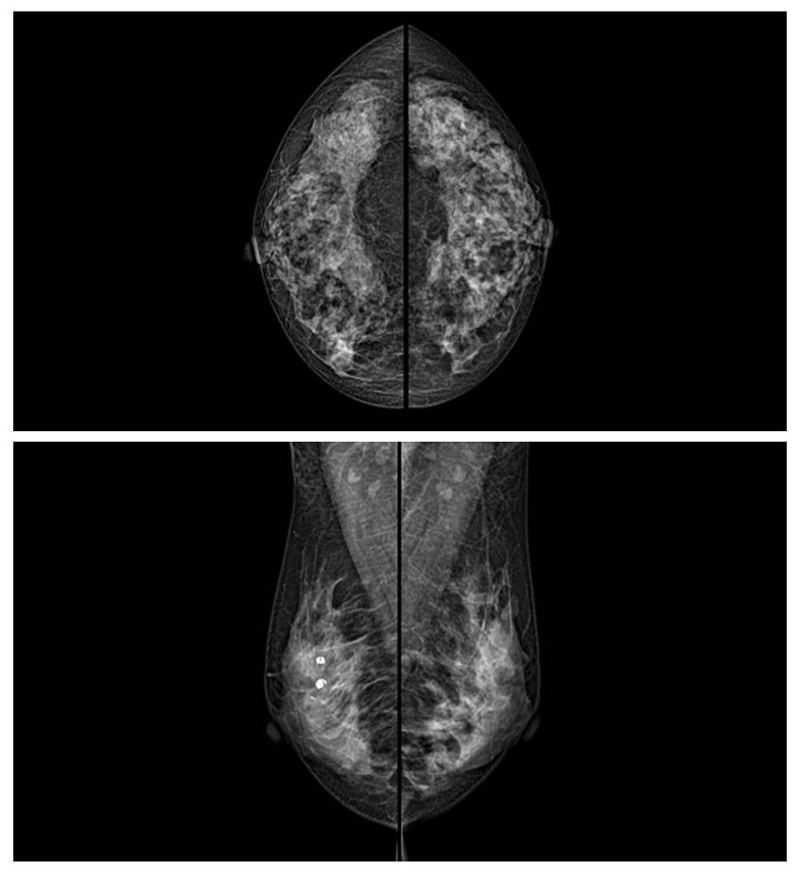

乳腺癌的发生率越来越高,已经是我们国家的癌症之一已成为女性健康“头号杀手”。乳腺DR可提高乳腺癌早期检出率并精准定位。发现和诊断早期乳腺癌最有效的方法之一,明显利大于弊女性都要重视乳腺的检查。辐射很小最简便、最可靠、无创性检查手段,做一次乳腺DR的剂量相当于7周的正常生活。尤其是对于40岁以上的女性尤为重要,那么乳腺DR是怎么进行检查的呢?我们来了解一下,为广大朋友在检查前有点心理准备。检查时候是避开经期的前后,月经来后的7天左右比较合适。需要脱衣服检查,根据拍片的摆位要求,有头尾位置,内外斜位,还有侧位。定点放大压迫方法可以更细微清晰的检查出病灶。